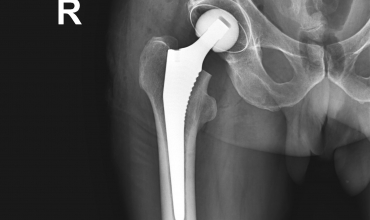

• Ендопротезування кульшового суглобу

Ендопротезування кульшового суглобу

Если постоянная боль в тазобедренном суставе мешает выполнять самые простые повседневные движения, нарушает ритм нормальной жизни, Вам необходимо обратиться за консультацией к специалисту ...